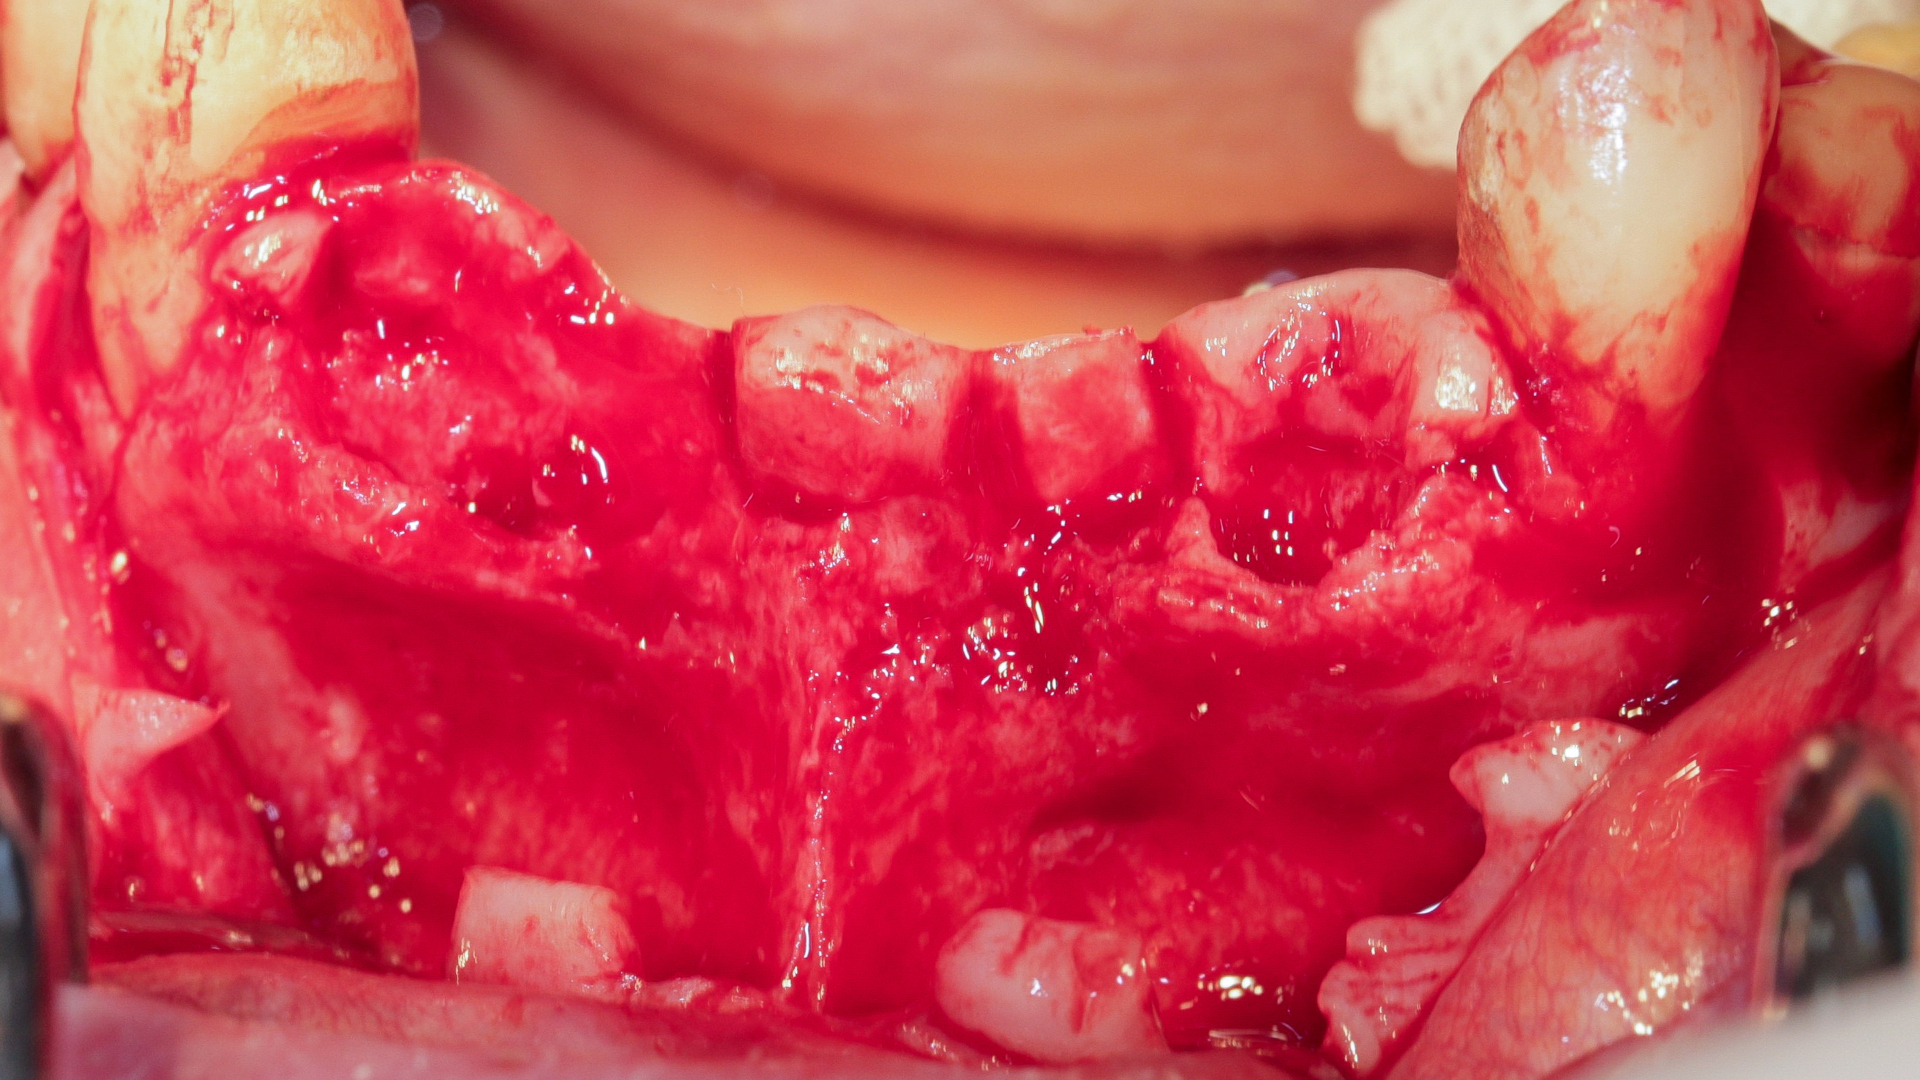

Nous réalisons un lambeau avec une incision crestale décalée en palatin en 11 et 21, sulculaire en 12, 13, 22, 23, en prenant soin de préserver les papilles interdentaires, ainsi que deux décharges verticales en distal des canines. Nous réalisons un décollement de pleine épaisseur (Figs. 28 et 29). Les dents (12, 22 et 18) sont facilement extraites et les alvéoles curetées avec soins. Deux implants (4*13) sont positionnés dans la paroi palatine des alvéoles, il subsiste une déhiscence vestibulaire en 22. Les racines de 12, 22 et 18 sont séparées dans le sens de la longueur. Les racines préparées comme indiqué ci-dessus, sont vissées en vestibulaire et en occlusal de la crête, au moyen de vis d’ostéosynthèse (diamètre 0,9 mm), afin de reconstruire la crête osseuse au niveau des inters de bridge ainsi que la paroi vestibulaire de la crête au niveau de 22 (Figs. 30 et 31). Le gap vestibulaire entre les implants et la crête ainsi que l’espace entre la crête et le greffon au niveau de 21, sont comblés avec un matériau d’origine synthétique (Collapat II Symatese). Le lambeau est tracté, suturé coronairement avec un fil tressé synthétique 5.0 (Fig. 32). Des piliers coniques droits pour prothèse plurale transvissée sont posés, et une empreinte prise à la fin de l’intervention (Fig. 33). Un provisoire est réalisé dans la journée par notre laboratoire de prothèse et posé le soir même. (Figs. 34 et 35)

Fig. 28